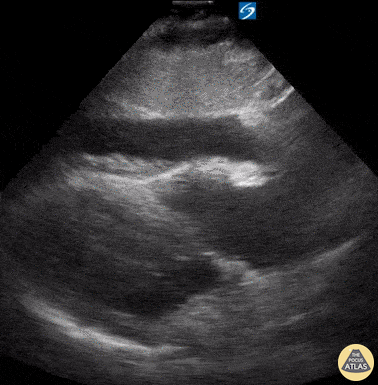

Pericardial Disease - Circumferential Pericardial Effusion with Tamponade

Seen here is the subcostal view of a patient with hemodynamic compromise. Note the circumferential area of anechoic fluid, resulting in dynamic right atrial and ventricular collapse as well as global hyperdynamic systolic function. It is important to remember that systolic right atrial collapse may be the earliest echocardiographic sign of tamponade. Diastolic right ventricular collapse indicates decreased cardiac output as a consequence of inappropriate right ventricular filling. Rupinder Sekhon, MD Central Michigan University, Emergency Medicine